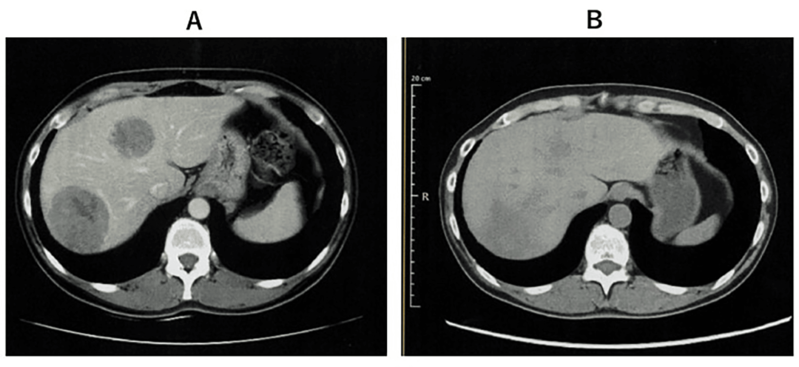

2、第 338 天胸部 CT 显示,原发和复发病灶缩小;

3、第 479 天 PET-CT 仅残留两个小转移灶,截至报道时,患者无进展生存期已超 577 天,生活正常。